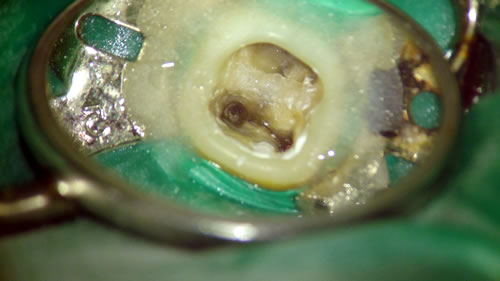

ラバーダム精密根管治療

ラバーダムとは、写真のように、歯を周りの組織と隔離するための隔離シートのことです。

根管治療は細菌除去との闘いですので、治療対象の根管を他の組織と隔離した環境で行わないと、根管に唾液が0.01ml入ってしまっただけで失敗してしまうのです。

当院で根管治療を行う際は、ラバーダムを使用できる場合はラバーダムをして感染防止をしながら根管治療を行います。